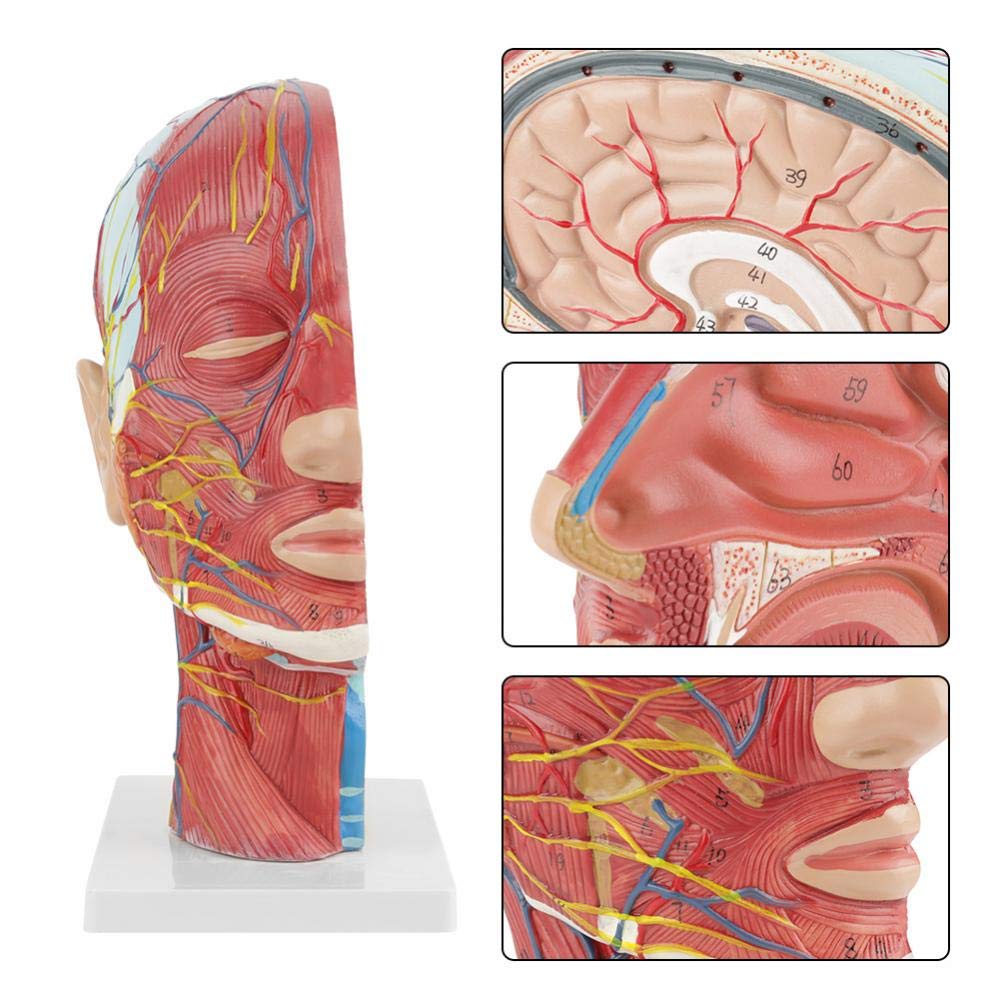

| Caracteristici | Modelul arată morfologia locală a laturilor interioare și exterioare ale secțiunii sagitale mediane a capului și a gâtului, precum și a structurilor vaselor de sânge și a nervilor și există 84 de părți care indică semne în total. |

【1: 1 LIFESIZE】 Secțiune mediană din 1: 1 Modelul mușchiului vascular neural superficial al capului mare și al gâtului natural (partea dreaptă). Manopera fină. Oferind o gamă completă de caracteristici anatomice.

【Model de mușchi neurovascular superficial】 extrem de detaliat, numere marcate, detașabile, adânciți înțelegerea mușchilor superficiali, vaselor, nervilor și structurilor interne ale capului și gâtului. Red-Artery, vene albastru, galben-port.

【Caracteristici】 arată mușchii superficiali ai feței expuse; vasele de sânge superficiale și nervii feței & scalp; structurile interioare ale glandei parotide și ale tractului respirator superior; Structura de secțiune sagitală a coloanei vertebrale cervicale.

Acest model arată detalii despre gâtul dreptului drept și secțiunea sagitală mijlocie a omului. inclusiv superficialul

mușchii feței expuse; vasele de sânge superficiale și nervii feței și ale scalpului; Structurile interioare

a glandei parotide și a tractului respirator superior; Structura de secțiune sagitală a coloanei vertebrale cervicale.

Modelul a arătat morfologia locală a secțiunilor sagitale mediale și laterale ale capului și gâtului și ale structurilor sale vasculare și nervoase, cu un total de 100 de indicatori de sit.

Acest model este un model natural de mușchi neurovascular superficial al capului și gâtului, 1 componentă, care arată detaliile capului drept și gâtului drept și secțiunea sagitală mediană, inclusiv mușchii superficiali expuși ai feței, vasele superficiale ale feței și scalpului, nervii și structura medială a glandei parotide și a tractului respirator superior și a structurii secțiunii sagitale a coloanei vertebrale cervicale